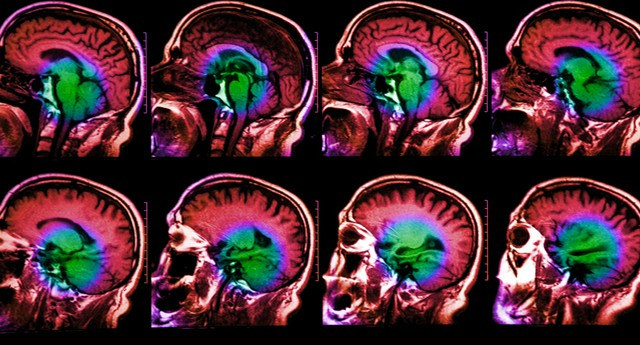

Nghiên cứu này là một phần của lĩnh vực “Imaging genetics” (hình ảnh di truyền học) còn khá non trẻ nhưng đang phát triển, nhằm mục đích tìm hiểu tác động liên quan đến biến đổi giữa di truyền với sự thay đổi trong giải phẫu não và chức năng não.